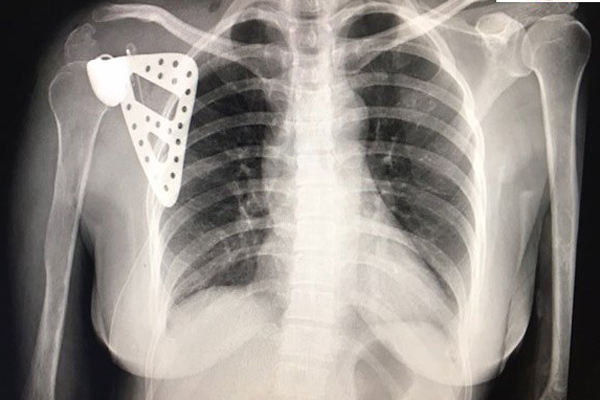

Chủ quan với cơn đau bả vai, cô giáo Hà Nội bị ung thư xương mà không biết

- Chị Thúy chịu đựng cơn đau âm ỉ như kiến cắn ở bả vai suốt 5 năm. Chỉ đến khi không nâng tay được mới đi khám, bác sĩ kết luận đã bị ung thư.

Nam bệnh nhân 35 tuổi đi khám vì đau khớp háng, đi lại khó khăn. Khi đến BV Bạch Mai khám, bác sĩ phát hiện, tế bào ung thư đã chạy lên tận não.